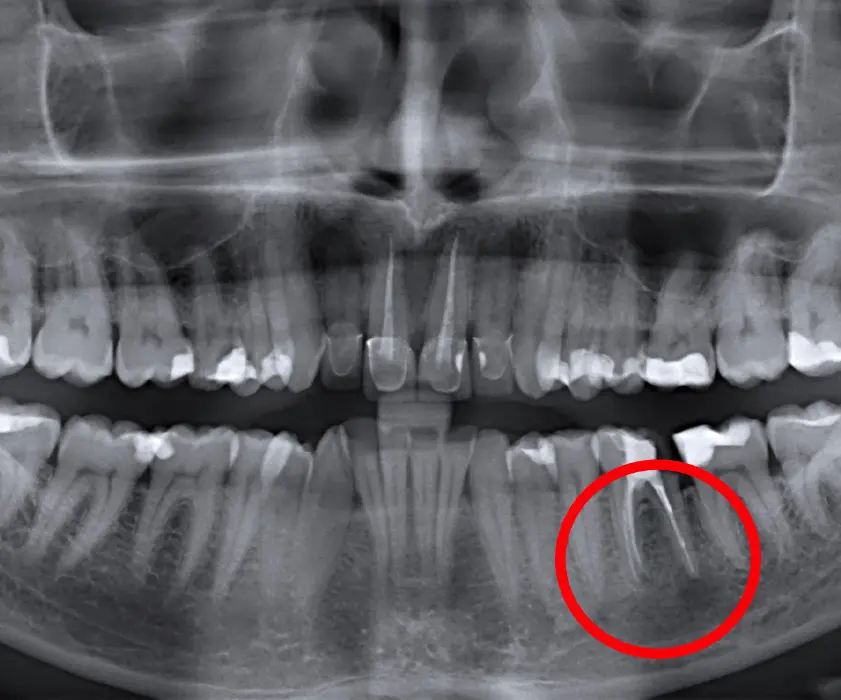

Jaki bolovi i otekline mogu biti prouzročeni zbog periapikalnih lezija zuba, tj. apscesa, granuloma ili različitih cisti, odnosno tvorevina i promjena koje su vidljive oko korijena zuba. Takve promjene se najčešće dijagnosticiraju uvidom u ortopan snimku, a uklanjaju se oralno kirurškim zahvatom – cistektomijom.

Pri dijagnosticiranju dentalne situacije i planiranju kirurške terapije primjenjuje se suvremena rendgenska dijagnostika – panoramska snimka (ortopan), ciljana snimka uz RVG ili 3D dijagnostika korištenjem CT-a. Sva rendgenska tehnologija koju koristimo smatra se najnovijim rješenjima na tržištu te jamči visoku preciznost u dijagnostici i planiranju stomatološke terapije za bilo koji dentalni problem.